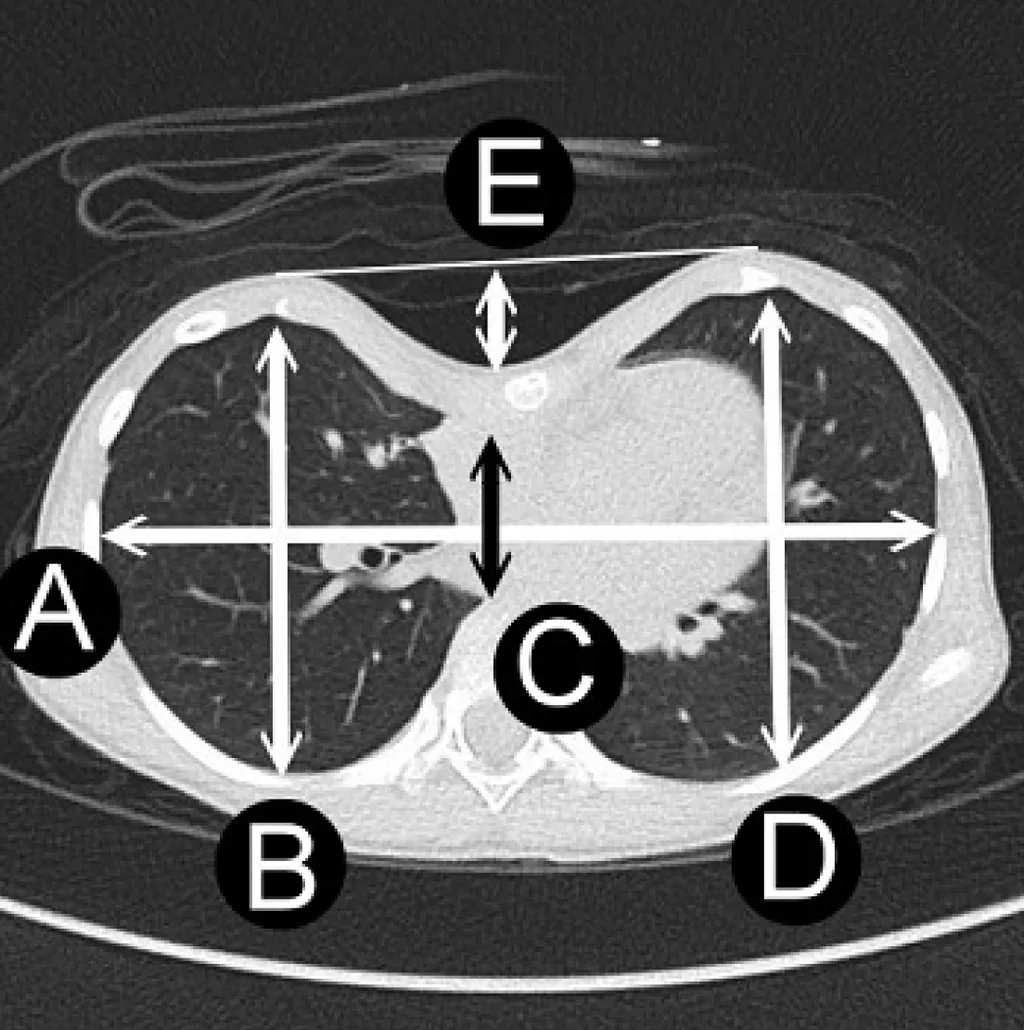

詳解

破題關鍵

這題的解題核心在於精確辨識圖片中代表胸廓「最大橫徑」與「最小前後徑」的標示,Haller index就是這兩者的比值。圖片中白色橫向雙箭頭線長度A代表最大橫徑,黑色縱向雙箭頭線長度C代表最小前後徑。

選項拆解